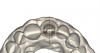

(38.) Convex intaglio surface.

Figure 38

(39.) Convex intaglio surface.

Figure 39

(40.) Convex intaglio surface.

Figure 40

(41.) Convex intaglio surface.

Figure 41

The profiles of the intaglio surfaces facing edentulous areas should be convex like modified ridgelap and ovoid pontics, so these surfaces are accessible and cleanable (Figure 38 through Figure 41).